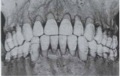

Andrews Six Keys of Occlusion

Andrews کوشید تا با تعریف کلید های شش گانه اکلوژن ایده آل به جای اکلوژن نرمال، معیاری از وضعیت بسیار عالی اکلوژن دندانی برای اهداف درمانی فراهم آورد که عبارتند از:

1. Molar Relationship: کاسپ مزیوباکال مولر اول بالا با شیار بین کاسپ مزیوباکال و کاسپ میانی باکال مولر اول پایین جفت می گردد. کاسپ دیستوباکال مولر اول بالا با کاسپ مزیوباکال مولر دوم پایین تماس دارد.

2. Crown Angulation: تاج تمامی دندان ها، زاویه ی مزیالی دارد.

3. Crown Inclination: بیانگر شیب لبیولینگوالی یا باکولینگوالی تاج دندان ها می باشد.

A: شیب ثنایا ها به سمت سطح باکال یا لبیال می باشد.

B: دندان های خلفی بالا-کانین تا پرمولرها- شیب لینگوالی دارند. شیب تاج مولرهای بالا مختصری بیشتر از کانین ها و پرمولرها می باشد.

C: دندان های خلفی پایین بطور افزایشی از کانین تا مولرها دارای شیب لینگوالی می باشند.

4. Rotation: در سیستم دندانی بالغ چرخش های دندانی وجود ندارد.

5. Spaces: هیچ گونه فضایی بین دندان ها وجود ندارد.

6. Occlusal plane: پلان اکلوزال ممکن است صاف یا مختصری دارای انحنا باشد.